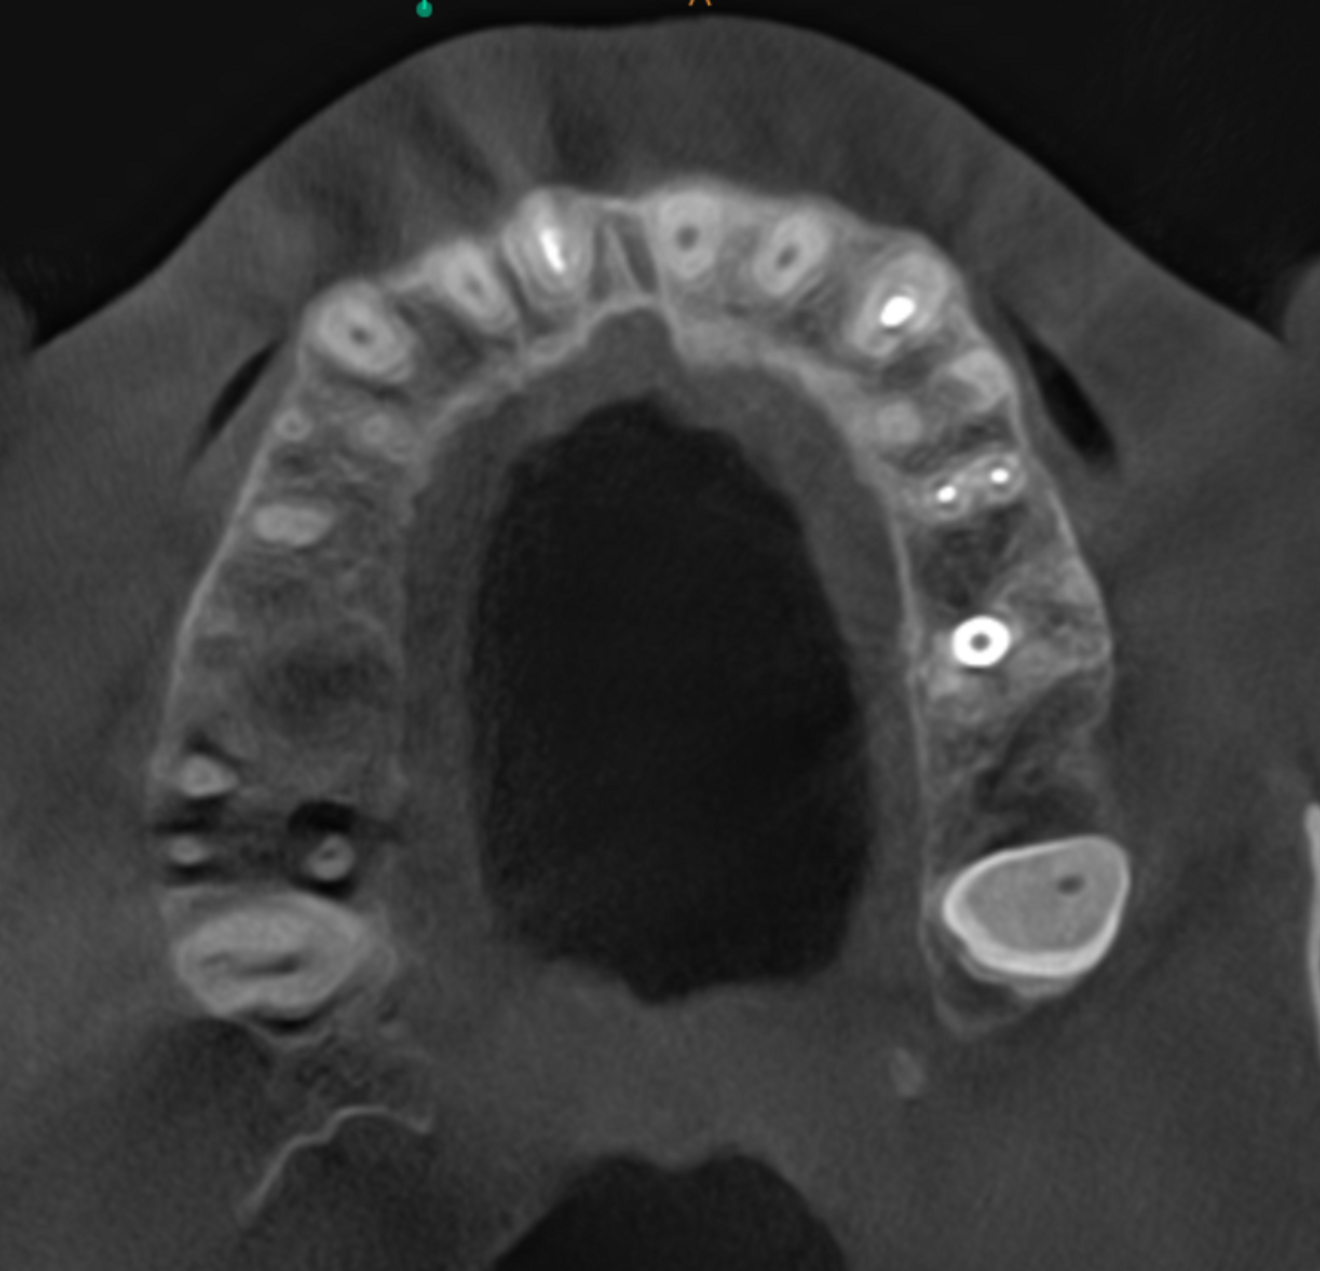

Fig. 5a: Large-volume CBCT scan. Transversal cross-section of the maxilla showing bone loss around the roots of tooth #17 and cortical wall damage.

Fig. 5b: Low-level transversal cross-section of the maxilla showing full involvement of the maxillary sinus.

Fig. 5c: Mid-level transversal cross-section of the maxilla showing full involvement of the maxillary sinus.

As a first step, we informed the patient about our findings on the new CBCT scan and explained the severity of his dental condition and paranasal sinusitis (Figs. 5a-f). We immediately referred him to a hospital otolaryngology department for microbial examination and proper antibiotic treatment. After nine days of a high-dose amoxicillin and clavulanic acid therapy, the endodontic treatment could be started.

Right after the opening of the pulp chamber, a strong odour emanated from the oral cavity. This was to be expected given that the CBCT scan showed four relatively wide canals and a large pulp chamber in this second molar—features often associated with necrosis and bacterial accumulation. The pulp chamber was rinsed with copious amounts of sodium hypochlorite. Before shaping of the orifices, the tooth was rinsed with saline, followed by a 17% EDTA solution. I prefer to use the Traverse orifice opener (Kerr Dental) to prepare cone-shaped orifices. Its specialised flute design and heat treatment provide reliable flexibility and strength and support debris removal. The working length was then determined in each canal with a #10 K-file and electronic apex locator. The precise determination was essential in this case because the maxillary bone had been damaged by the inflammation around the apices on both the buccal as well as the palatal sides, penetrating into the maxillary sinus.